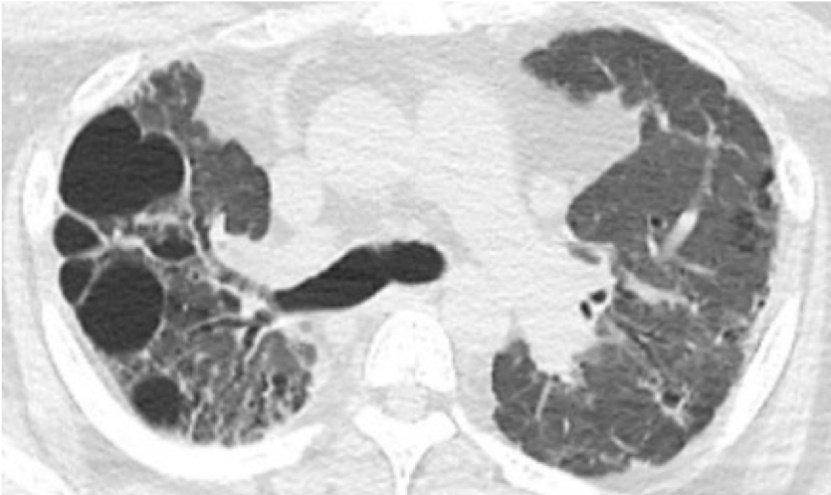

サルコイドーシスの肺野病変の高分解能CT像

気管支・血管束に沿って広がる粒状影および線状影束。一部は肉芽腫病変を反映し、ステロイド薬の効果が期待できる。